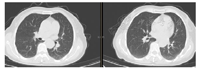

1个月后复查胸部显示左肺实变完全吸收痊愈。

综上,一家四口人,三人发热,两人确诊鹦鹉热,一人临床疑诊鹦鹉热。确诊二人出院1个月后门诊随诊,复查CT肺部实变完全吸收(图3、图4)。